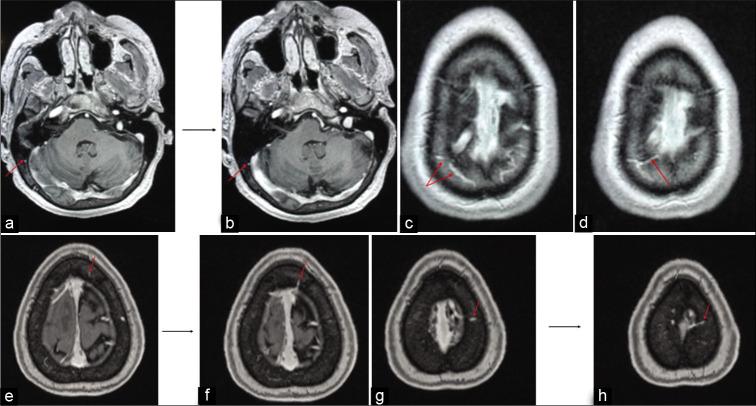

High-resolution, T1-weighted MRI scans from 20 adult and 16 pediatric subjects were selected for analysis. Skulls were divided into four regions, that is, frontal, parietal, temporal, and occipital. On each scan, a trained observer counted all diploic veins in every skull region. Each diploic vein was also followed to determine its final drainage pathway (i.e., dural venous sinus, dural vein, LL, or indeterminate).

In the adult age group, the frontal and occipital skull regions showed the highest number of diploic veins. However, the highest number of draining diploic veins connecting to the lacunae lateralis was found in the frontal and parietal skull region, just anterior and just posterior to the coronal suture. In the pediatric age group, the parietal skull region, just posterior to the coronal suture, showed the highest overall number of diploic veins and also the highest number of draining diploic veins connecting to the LL.

This study suggested that diploic venous density across the skull varies with age, with more parietal diploic veins in the pediatric age range, and more occipital and frontal diploic veins in adults. If the DVS is ultimately used for CSF diversion, our anatomical data point to optimal sites for the insertion of specially designed intraosseous infusion devices for the treatment of hydrocephalus. Likely the optimal sites for CSF diversion would be the parietal region just posterior to the coronal suture in children, and in adults, frontal and/or parietal just anterior or just posterior to the coronal suture.